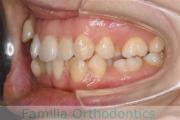

No.22V-449

- 主な症状:

- 上顎前突

- その他の症状:

- 叢生

- 年齢:

- 14歳

- 性別:

- 男性

- 抜歯部位

- 上:

- 44

- 下:

- 8448

- 主な使用装置:

- FEA

- 治療にかかった費用:

- 87万円

歯並びをきれいにしたいということで来院されました。上下左右から小臼歯を抜歯して、マルチブラケット法を行っています。2年弱、25回程度の通院が必要でした。

かなり強い叢生(でこぼこ、凹凸、ガタガタ)ですので、保定をしっかりしないと後戻りのリスクがあります。

- ≫治療前

-

上顎

下顎

前歯の関係など

右側

正面

左側

- ≫治療後